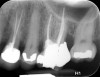

Clinical procedure: If apical bone loss is present (Figure 1) a collagen/gelatin sponge (eg, Gelfoam®, Pfizer Inc., www.pfizer.com) can be placed apically so that the MTA can be delivered to the desired working length. (Any other surgical resorbable sponge would also work, such as OraPlug® [Salvin Dental Specialties, www.salvin.com], Surgifoam® [Midwest Dental, www.mwdental.com], or Surgispon® [Aegis Lifesciences, www.surgispon.com]). This is done by taking a small piece (2 mm x 2 mm) of the resorbable sponge and pushing it down to and through the root apex with an endodontic file. Once this is done, MTA is packed down the canal with a custom-fitted cone. The clinician can use a rubber stopper on the gutta-percha cone to know the exact length of MTA placed in the apical third (Figure 2). Once the apical third is sealed with 3 mm to 5 mm of MTA, the remaining coronal canal space can be back-filled using a warm gutta-percha technique (Figure 3).

Fig 1. Preoperative radiograph showing apical bone loss.

Figure 1